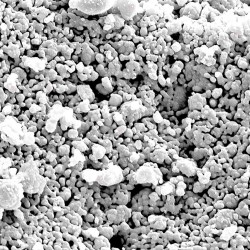

SUPERFICIE MUY RUGOSA E HIDRÓFILA 100% SINTÉTICO Y REABSORBIBLE PROPIEDADES OSTEOCONDUCTIVAS IDEALES

Superficie muy rugosa e hidrófila 100 % sintético y reabsorbible, propiedades osteoconductivas ideales.

Porosidad interconectada ultra alta

Elección del tamaño de partícula

Las pequeñas partículas de maxresorb ® (0,5 – 1,0 mm) permiten una buena adaptación a los contornos de la superficie; son especialmente útiles para aumentos laterales o para llenar huecos cuando se trabaja con bloques de hueso autólogo. Para elevación de seno nasal y aumentos extensos, se recomienda el uso de partículas grandes de maxresorb ® (0,8 – 1,5 mm). El mayor espacio entre las partículas grandes permite una mejor vascularización y mejora la regeneración de defectos más grandes.